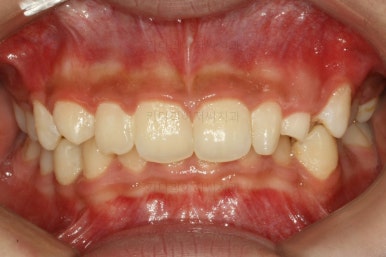

마찬가지로 부산교정치과 키다리아저씨치과에 처음 내원하셨을 당시의 입안 모습입니다.

화살표로 표시된 치아가 작은 앞니 부분인데 크기가 매우 작고 뾰족한 것을 볼 수 있어요. 유치가 아니고 평생 써야 하는 영구치입니다. 이러한 상태를 "왜소치"라고 표현하는데, 치아 크기의 문제로 여러 가지 문제점이 생길 수 있어요.

또 다른 문제는 위아래 앞니가 매우 많이 겹쳐져 있어서 아래 앞니가 거의 보이지 않는다는 점입니다.

부산교정치과 키다리아저씨치과에서 치료한 이번 치료의 전후사진을 비교해 볼게요.

왼쪽이 치료 전, 오른쪽이 치료 후 모습입니다.